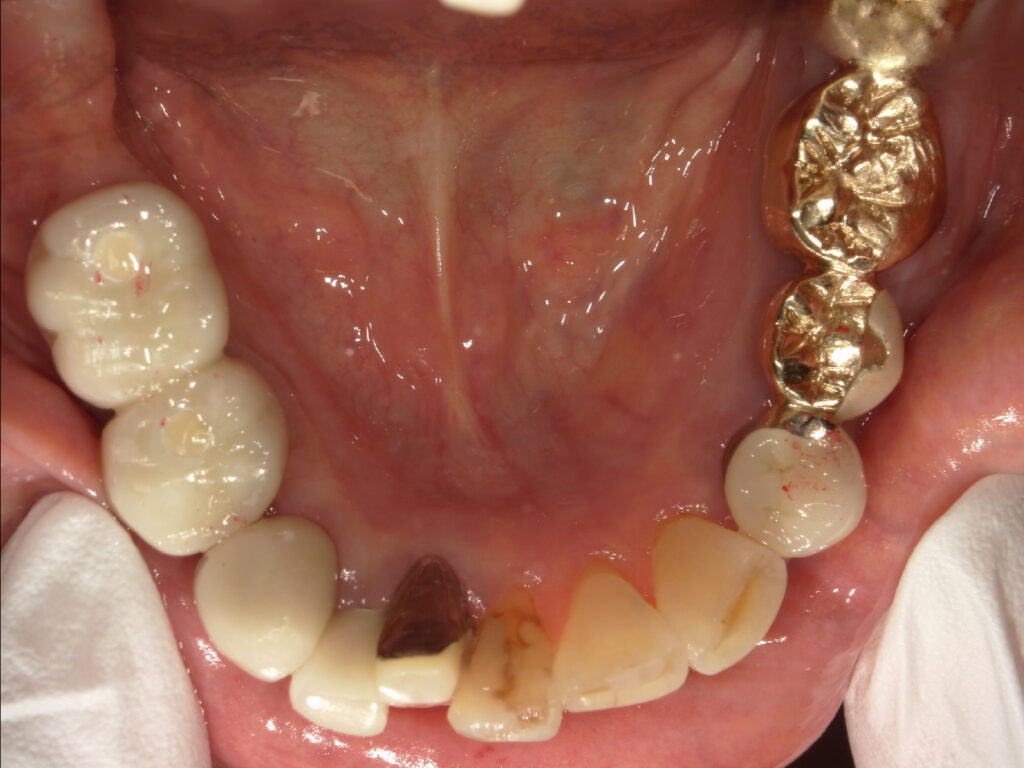

右下奥歯を2本インプラント治療した症例

| 主訴 | 右下欠けた、歯が緩む |

| 年齢 | 80代女性 |

| 治療内容 | 歯根嚢胞が大きく根管治療では限界のため抜歯しインプラント治療へ。 歯槽骨の量が不足している場合に、人工骨や自家骨を移植し、特殊な膜で覆うことで骨の再生を促し、インプラントを埋入できるようにするGBRという治療法も併用。 |

| 抜歯部位 | 右下4.6 |